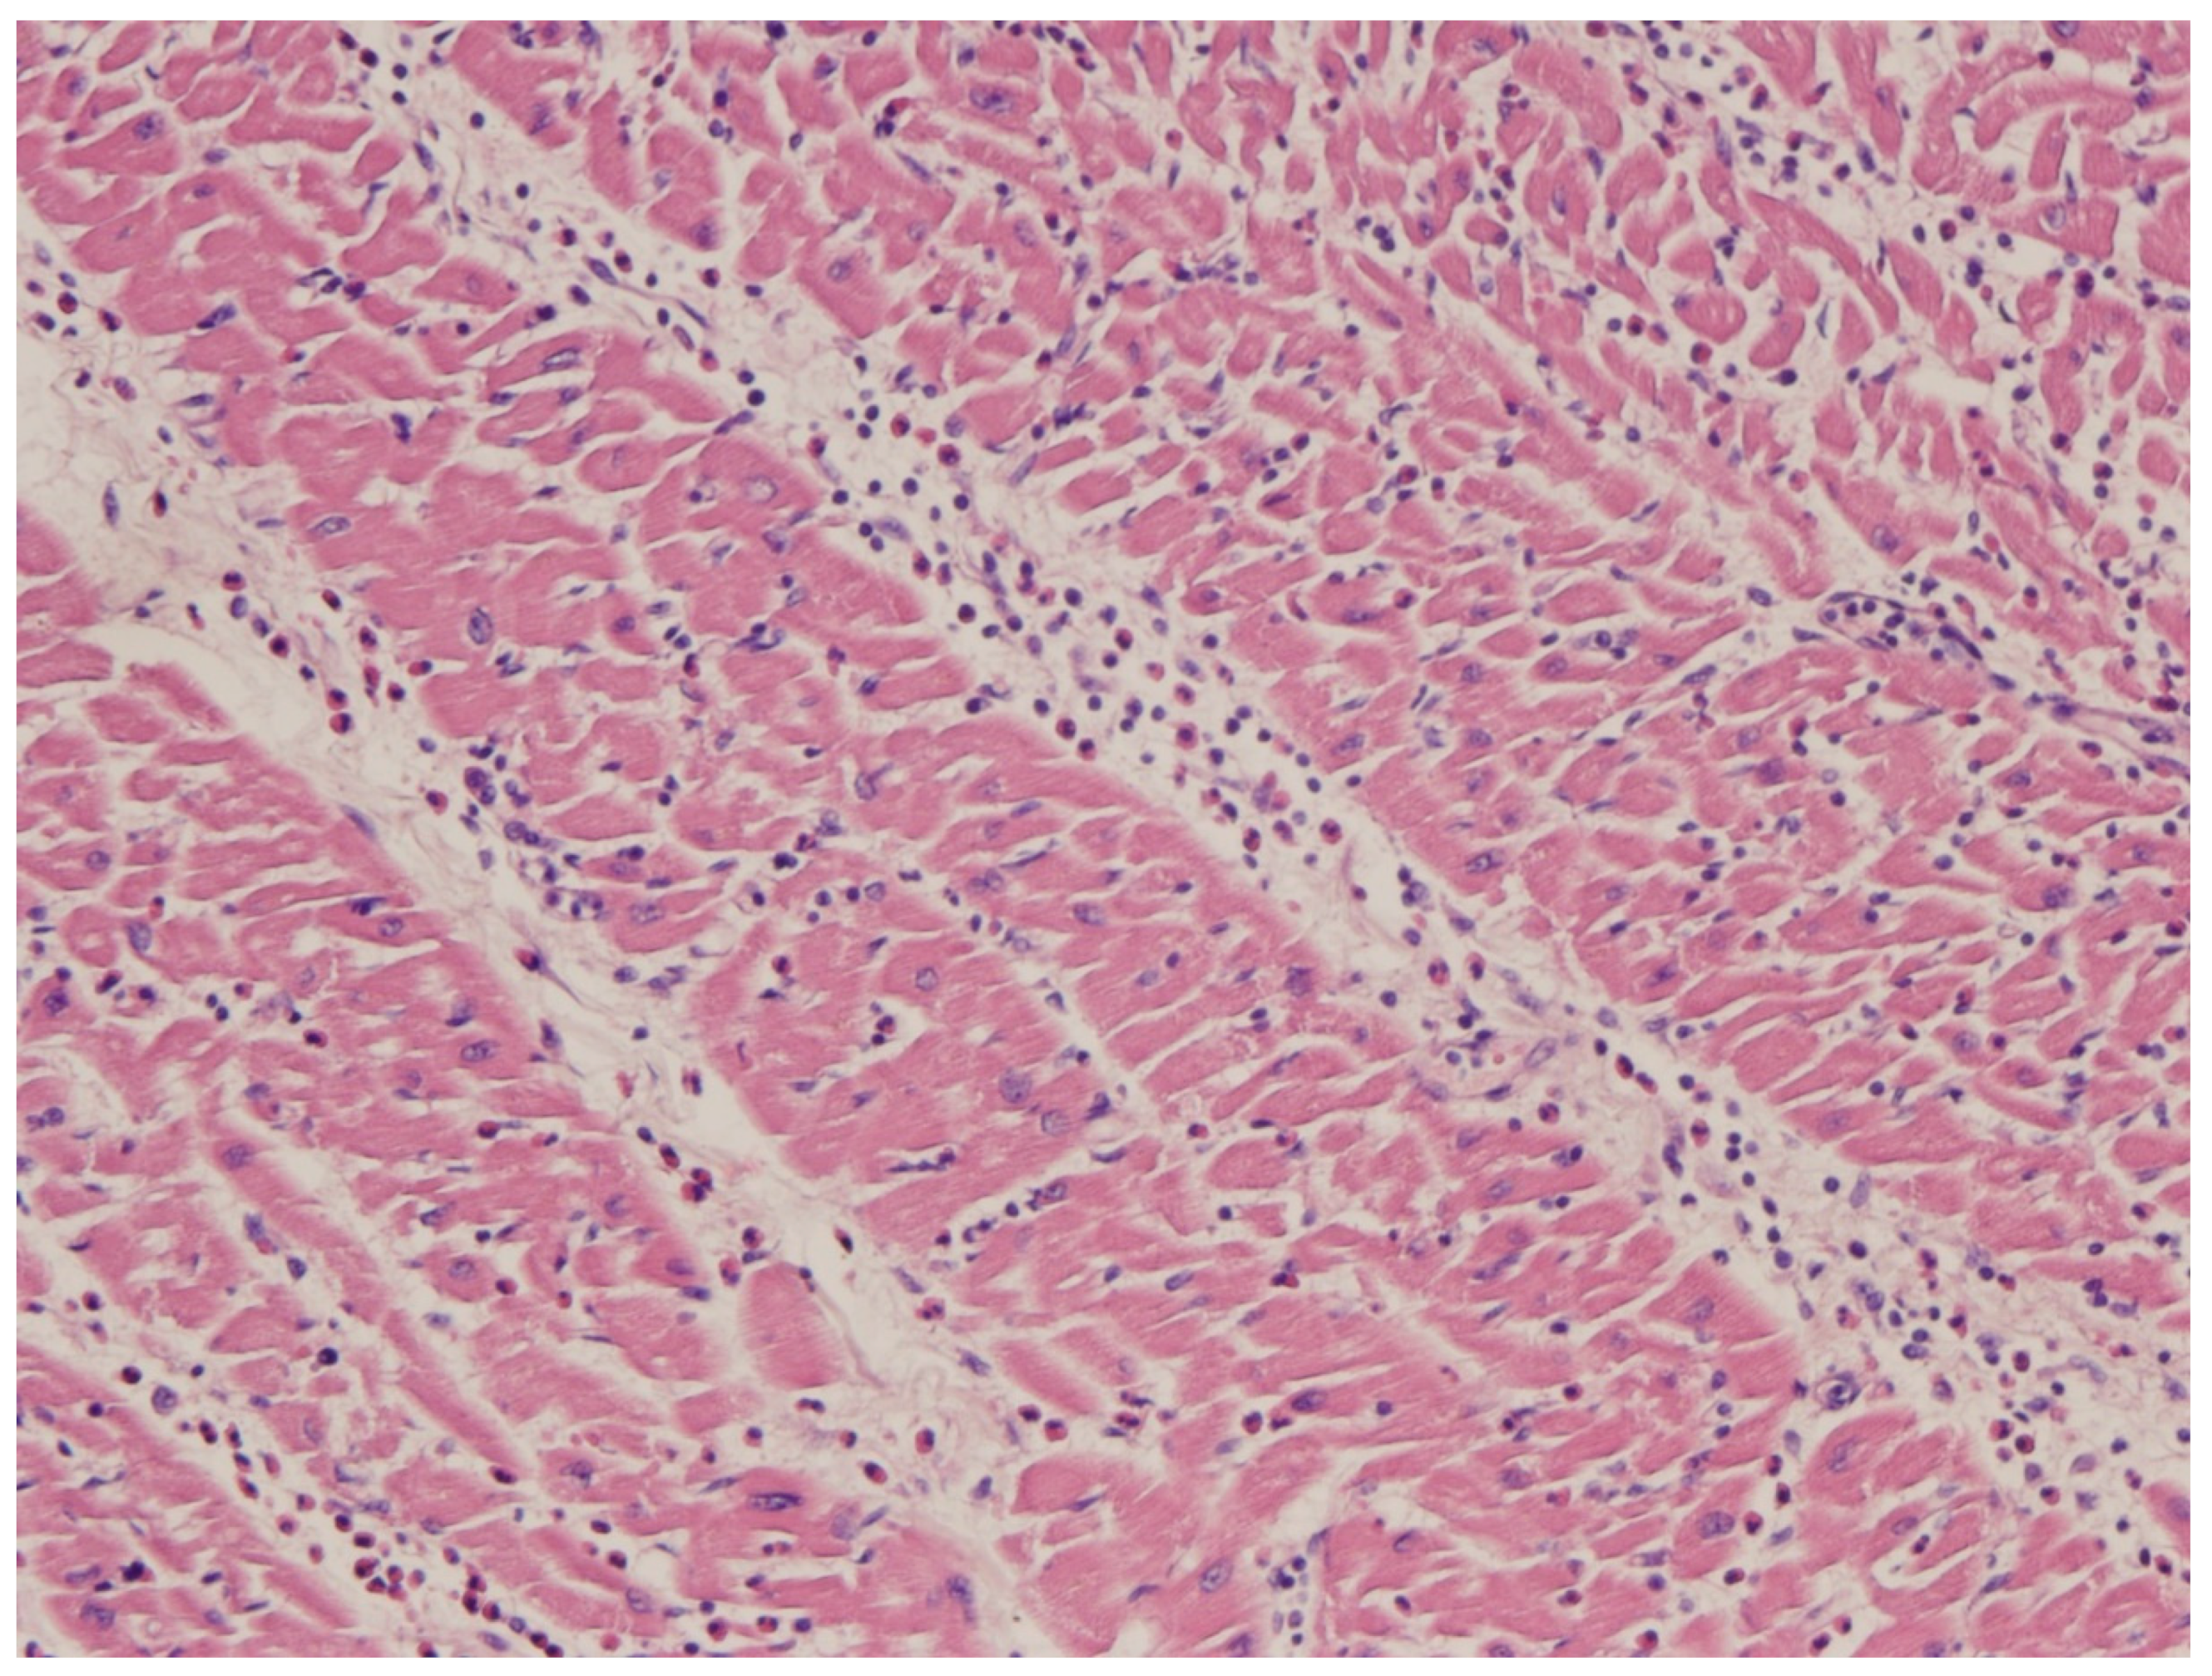

| 1987 | Aretz HT et al. Myocarditis: a histopathologic definition and classification. [23] |

- Aretz, H.T.; Billingham, M.E.; Edwards, W.D.; Factor, S.M.; Fallon, J.T.; Fenoglio, J.J., Jr.; Olsen, E.G.; Schoen, F.J. Myocarditis: A histopathologic definition and classification. Am. J. Cardiovasc. Pathol. 1987, 1, 3–14. [Google Scholar] [PubMed]